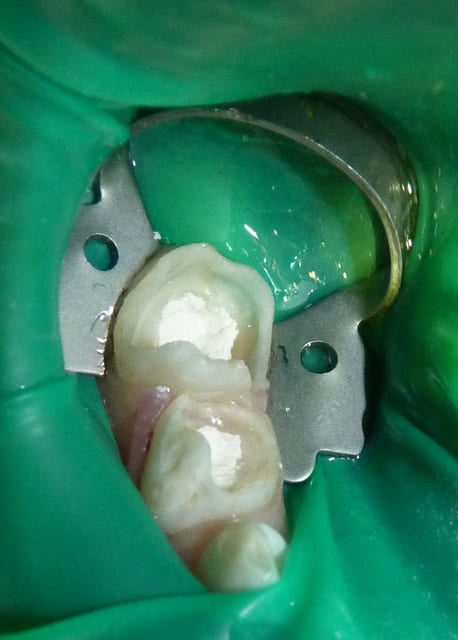

05/07/11 : secteur IV.

85 n'a plus de parois vestibulaire/linguale. 84 n'a plus de paroi linguale.

J'utilise un composite plutôt qu'un CVI pour une meilleure adhésion et résistance mécanique sur ces dents très délabrées. J'essaie de recréer des bombés sur les moignons.